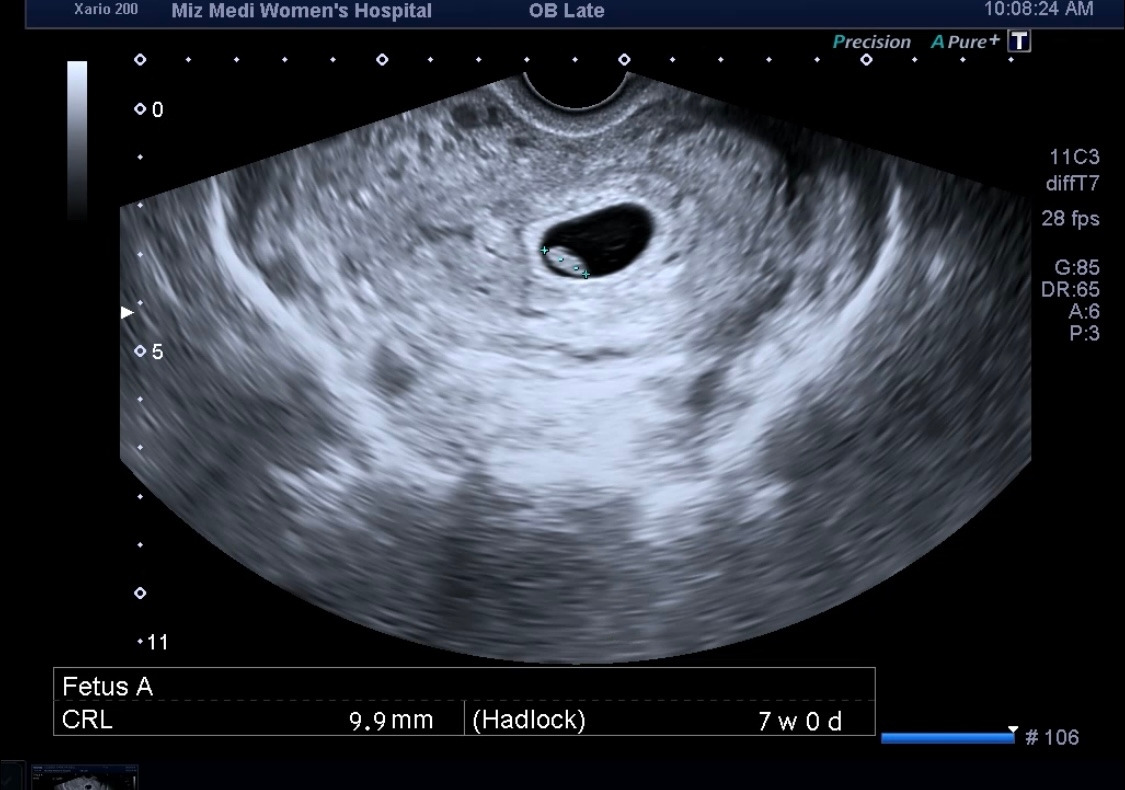

7주 차 너의 심장소리를 듣다.

9.9mm 1cm가 겨우 되는 작은 몸에서 나오는

쿵쾅거리는 심장소리란,

정말 꽤나 감격의 순간이었단다.

7주 차의 아가는 블루베리 정도 크기라고 하더라,

5주 차 때 아기집만 보였었는데, 10mm

7주 차에는 아가가 보였다. 9.9mm 아기집만큼 컸구나.

그리고 난황도 보여줬다.

주차는 생리가 일정해서 그런지, 어플과 100% 일치하였고, 예정일도 변함없이 고정되었다.

의사 선생님께 여쭤보니, 이제 예정일은 고정이며 바뀌지 않는다고 하더라.